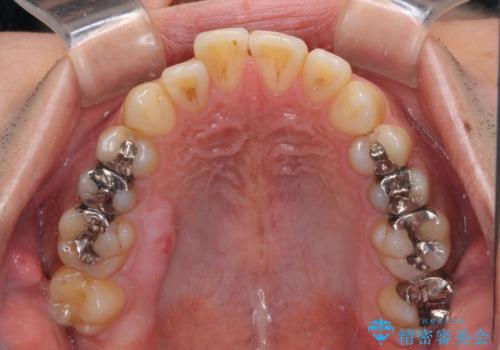

銀歯については、矯正治療により咬合関係を改善し、矯正治療後半に修復治療を行うこととしました。

修復治療後に細かい部分をインビザラインで再度仕上げるプランとしました。

銀歯のセラミック治療が1番の希望であったため、ここまで歯列がきれいに整うとは思ってなかったようで、大変喜んでいただけました。